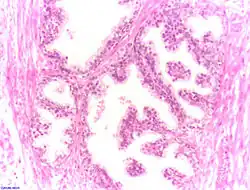

Der Querschnitt der Prostata kann in drei Zonen unterteilt werden, die sich in den Ausführungsgängen der Drüsen unterscheiden: die periurethrale Mantelzone, die Innenzone und die Außenzone. Die Ausführungsgänge der Drüsen in der inneren Zone enden direkt in die Harnröhre. Die Drüsen in der äußeren Zone sammeln ihr Sekret in gemeinsamen Ausführungsgängen, bevor sie in der Harnröhre enden. Diese Einteilung ist bei der Entstehung von Tumoren von Bedeutung (s. unten).

Die Ausführungsgänge (Ductuli prostatici) der Prostatadrüsen in der Prostata münden im Sinus prostaticus beidseits des Colliculus seminalis (Samenhügel) der Harnröhre. Ihr Drüsenepithel ist funktionsabhängig entweder einschichtiges Plattenepithel oder mehrreihiges hochprismatisches Epithel. Der Hohlraum (Lumen) der Drüsen enthält Concretio prostatica, konzentriertes geschichtetes Sekret.

Das Drüsenepithel setzt sich aus drei Zelltypen zusammen: am häufigsten sind basale und luminale sekretorische Zellen, die unterschiedliche Keratin-Subtypen exprimieren und sich dadurch unterscheiden lassen. Luminale Zellen zeichnen sich zudem durch die Expression von prostataspezifischem Antigen und Androgenrezeptor aus. Sehr viel seltener kommen als dritter Typ neuroendokrine Zellen vor, die anhand der von ihnen produzierten Neuronenspezifischen Enolase und verschiedener Neuropeptide identifiziert werden können. Stammzellen in der basalen Zellschicht bilden vermutlich die Vorläufer aller dieser Zelltypen.

Zwischen den Drüsen liegen glatte Muskelzellen, die sich bei der Ejakulation zusammenziehen und so das Sekret ausstoßen, und Bindegewebe mit elastischen Fasern, das sogenannte Stroma myelasticum prostatae.